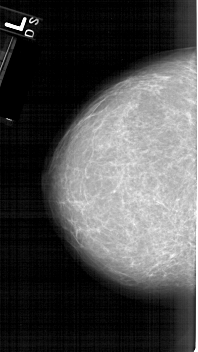

A_1610_1.LEFT_CC

LEFT_CC LINES 6331 PIXELS_PER_LINE 3556 BITS_PER_PIXEL 12 RESOLUTION 43.5 NON_OVERLAY